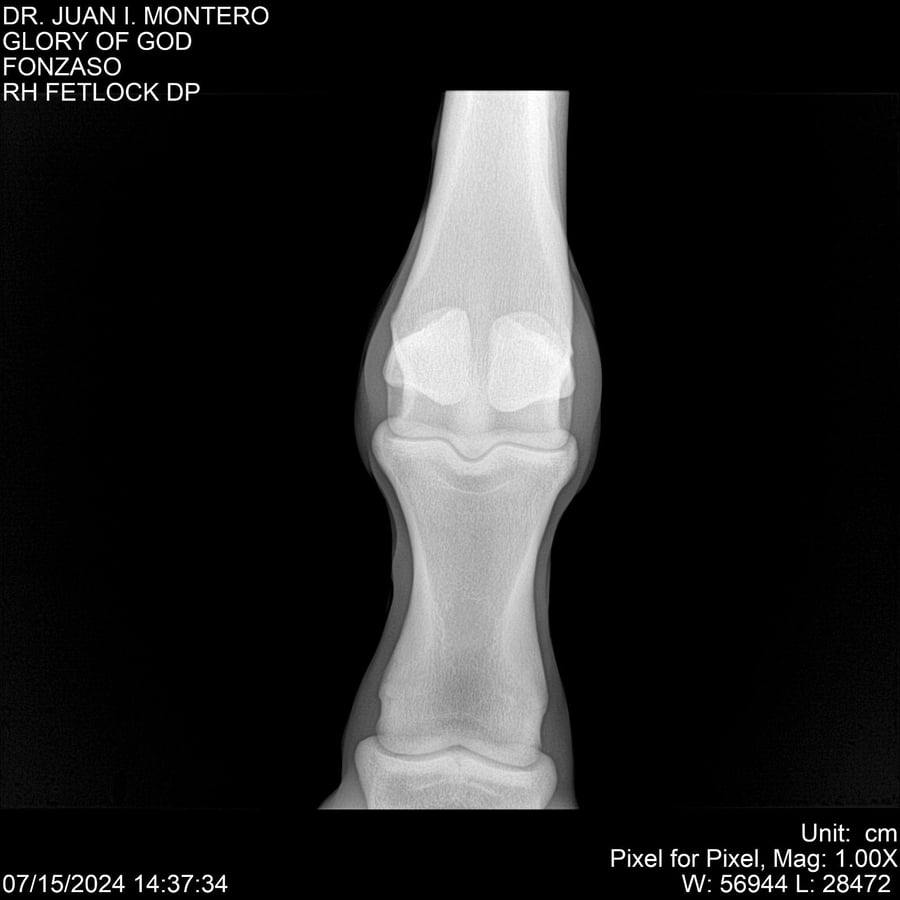

LOTE 10, GLORY OF GOD 🔥 🔥 🔥 Lote Anterior Volver al remate Lote Siguiente Ficha Contacto Montevideo - Ficha del Lote Identificador: #281389 Categoría: Yeguarizos Montevideo - 115 Visualizaciones ClicData Contacto Empresa: Abelenda N. R., Walter Hugo Nombre*: Teléfono* : E-mail* : Mensaje Enviar Registrese gratis Este contenido Exclusivo está disponible sólo para usuarios registrados Ingresar